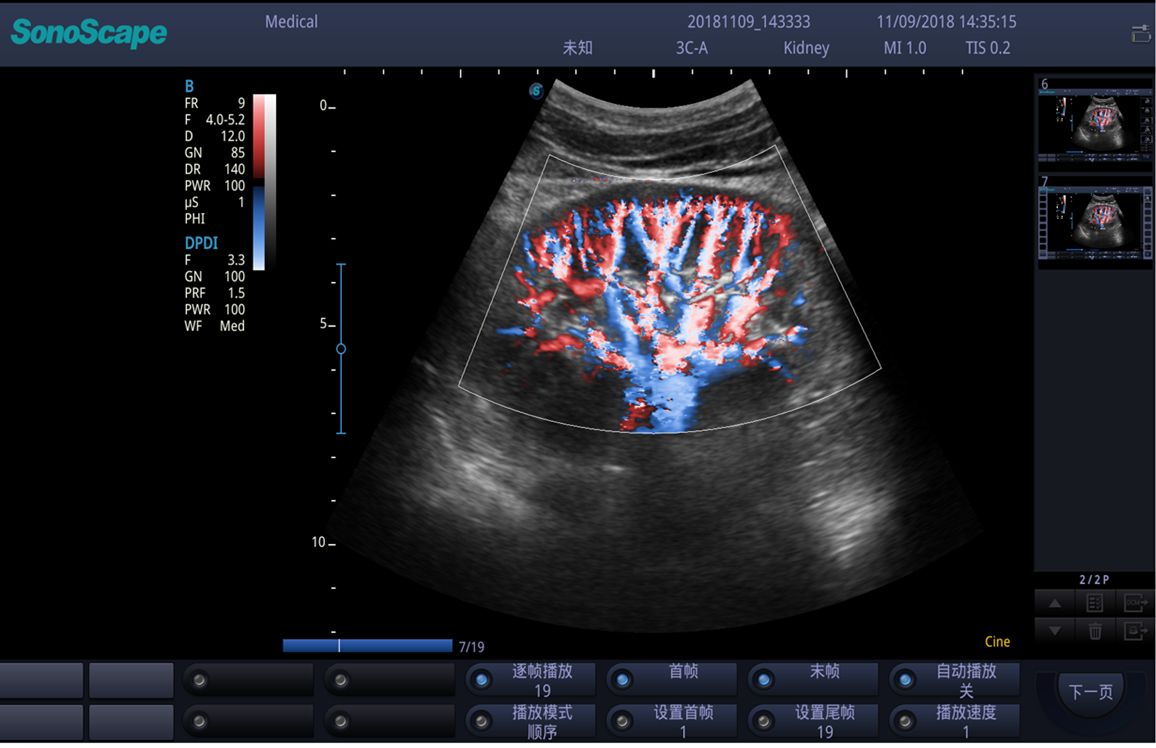

- Chế độ Doppler màu (CFM, PDI/DPDI): giúp đánh giá lưu lượng máu qua tim và mạch máu.

Chất lượng hình ảnh 2D trên máy siêu âm chuyên tim SonoScape P9:

Hình ảnh siêu âm Doppler thận sắc nét